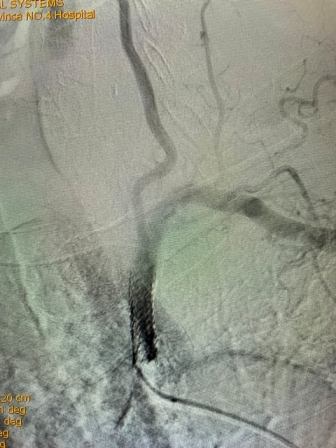

该患者是一位79岁老年男性,门诊以“头晕伴走路不稳”主诉入院。既往有高血压、冠心病PCT术后、慢阻肺病史。入院后完善相关检查,行B超检查考虑“左侧锁骨下动脉盗血”,进一步检查DSA全脑血管造影术时发现:“左侧锁骨下动脉闭塞,左侧锁骨下动脉盗血”。为解决患者疾病痛苦及改善其生活质量,神经内科任主任刘蔚玲主持召集专家团队讨论并精心安排,在客座教授刘亚民周密指导下,由神经内科侯有荣副主任医师、孟军鹏主治医师、赵荣健等骨干医生,通过开通闭塞处血管、球囊扩张后置入支架,手术顺利,术后造影显示患者左侧锁骨下动脉血流再通,锁骨下动脉盗血现象消失,血管再开通,患者术后无明显不适、后循环缺血症状消失。手术极大地改善了其生活质量,同时也有效地预防了严重的脑卒中事件的发生。

(术前造影) (手术后造影)

此例高龄患者、锁骨下动脉闭塞后再通、同时联合椎动脉狭窄病变的同期治疗,其手术复杂、难度大、风险高,神经介入手术创伤小,恢复快,效果立竿见影,其闭塞血管的顺利开通为预防其以后再发生脑梗死奠定了极为重要的基础。该例手术成功完成,再次标志着21点策略指南站 神经内科(卒中中心)神经介入技术水平更上一层新台阶。(采编 党委宣传部)